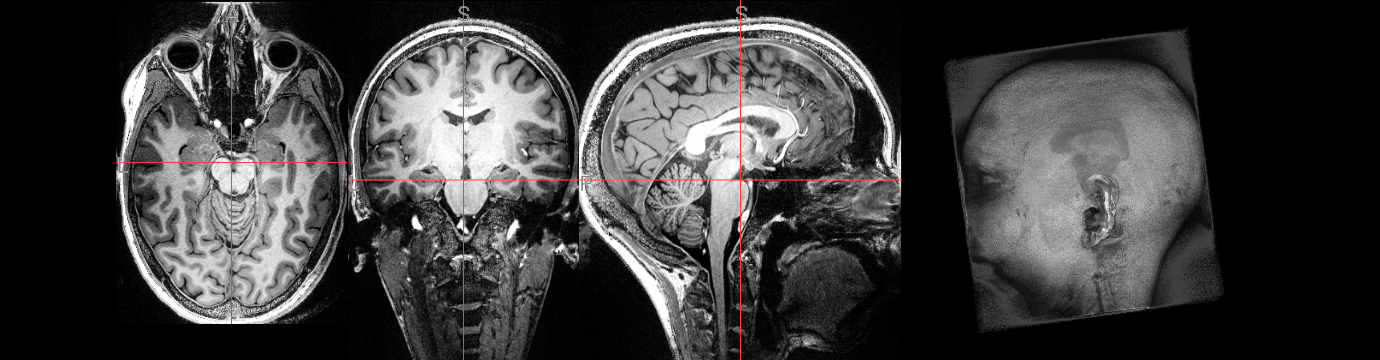

Inspect input data#

Here we define a function we will use to visualise NIfTI images so we can view some of the input data:

show_nii(glob("bids/sub-*/ses-*/anat/*mag*T2starw*nii*")[0], title="Magnitude", vmax=500)

show_nii(glob("bids/sub-*/ses-*/anat/*phase*T2starw*nii*")[0], title="Phase")

show_nii(glob("bids/sub-*/ses-*/anat/*T1w*nii*")[0], title="T1-weighted")